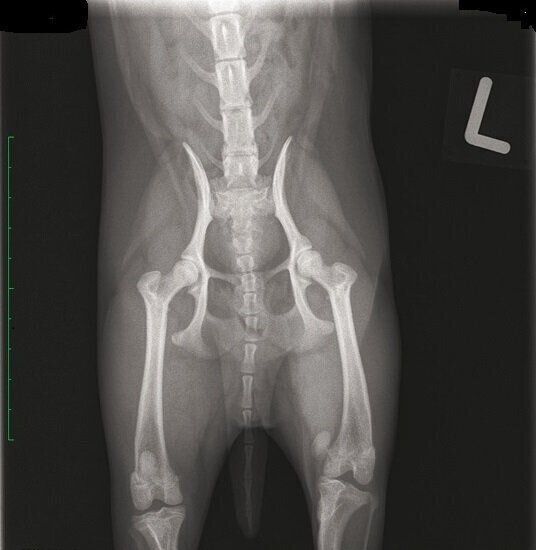

左足の膝蓋骨を脱臼している、生後9カ月のチワワのエックス線写真

健康な犬の膝関節は、「ひざのお皿」と呼ばれる膝蓋骨が、くぼみにはまった状態になっています。膝蓋骨脱臼は、この膝蓋骨がなんらかの原因によってくぼみからずれてしまう病気です。